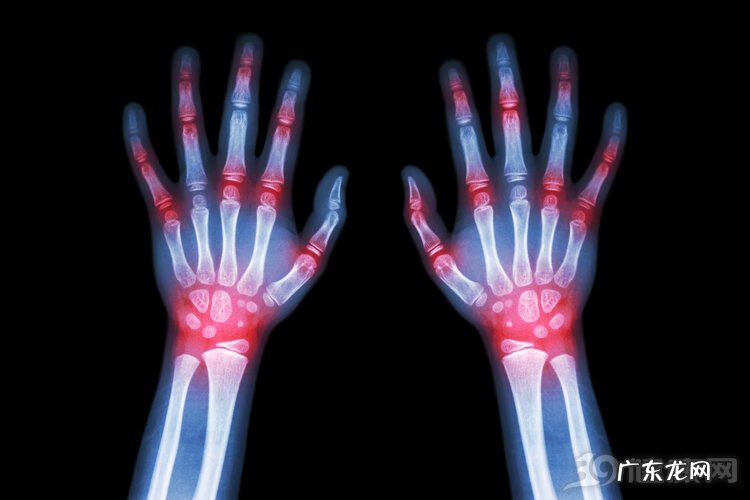

当血液中的尿酸积累得过多 , 就可能引起痛风 , 这个疾病相信大家不会陌生 。但是 , 我们要知道 , 尿酸高的危害远不止痛风 , 还包括肾结石、急慢性肾炎、心血管疾病、肝脏损害等 , 与此同时 , 还会加重“三高”(高血压、高血脂、高血糖) 。

有数据显示 , 血尿酸每增加60μmol , 发生高血压的风险会增加15%-23% , 急性肾衰的风险增加74% , 男女性冠心病的病死率分别增加17%、30% 。